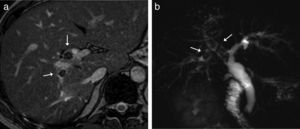

Enfermedades premalignasSe conocen 3 lesiones premalignas biliares: la neoplasia biliar intraepitelial, la neoplasia intraductal papilar de los conductos biliares y la neoplasia quística mucinosa o cistoadenoma5,24. La primera progresa a adenocarcinoma tubular y tiene carácter microscópico, por lo que no se diagnostica con imagen. La neoplasia papilar intraductal biliar incluye adenomas y tumores borderline y progresa hacia CC precoz (adenocarcinoma tubular o mucinoso), con mejor pronóstico que los carcinomas avanzados1,14. Crecen macroscópicamente dentro de la luz sin invadir la pared y se extienden superficialmente, por lo que pueden detectarse y caracterizarse con imagen. En muchos casos producen abundante mucina, que dilata difusamente los conductos biliares. Se han descrito 4 patrones de crecimiento (fig. 2): polipoideo, en forma de molde, superficial y quístico. Ningún estudio ha demostrado correlación entre los tipos de crecimiento, la localización, las características anatomopatológicas o la transformación en carcinoma invasivo24,25. Existen varios signos radiológicos que sugieren un crecimiento intraductal (fig. 3), como los nódulos o masas intraluminales, que suelen realzar más que el parénquima hepático, la ausencia de atrofia segmentaria y la multiplicidad de lesiones1,26. La dilatación biliar sin obstrucción completa se considera un hallazgo importante para diagnosticar estos tumores27. La RM con colangiografía tiene ventajas comparada con la TC y la colangiografía endoscópica27. Las imágenes de RM difusión pueden aportar información relevante tanto para distinguir las lesiones papilares de la bilis como para establecer la invasión tumoral27. Para determinar la extensión en los tumores con crecimiento superficial sin masas puede ser útil la colangioscopia17. Es importante plantear el tratamiento quirúrgico en función del tipo de crecimiento radiológico. Con la resección completa el pronóstico es más favorable que el del CC1. En el diagnóstico diferencial hay que incluir las litiasis, porque simulan una lesión intraductal. En ecografía, las litiasis presentan sombra en un 80% de los casos28. En TC es útil el estudio sin contraste para determinar la presencia de calcio o realce, ya que ambas entidades pueden tener atenuación variable. Los bordes irregulares, la estenosis ductal o el engrosamiento asimétrico de la pared apuntan al tumor papilar, mientras que los bordes finos y angulados son característicos de las litiasis28, que, además, tienen una señal baja en T1 y T2 (fig. 4), a diferencia de los tumores, cuya señal en T2 es mayor27.

Neoplasia intraductal papilar con crecimiento quístico. A) Imagen coronal de colangio-RM 2D que muestra una lesión quística (flecha), encapsulada, sin nódulos y sin clara comunicación con la vía biliar. B y C) Imágenes transversales de RM hepática eco de gradiente T1 con supresión grasa, sin y con contraste (gadobenato de dimeglumina) en fase hepatobiliar que muestran paso de contraste a la lesión (flecha) por comunicación con la vía biliar.